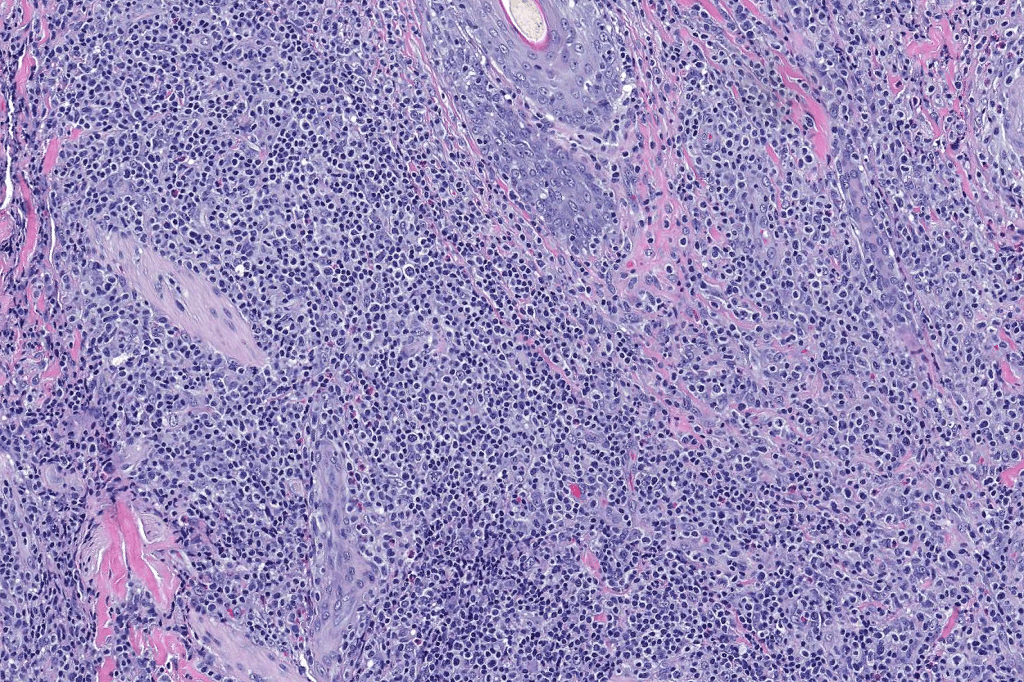

Histological features

•Subdivided into 5 major & several rarer variants

•Type A: 75-80%, wedge shaped infiltrate with base uppermost, large, anaplastic cells with abundant cytoplasm and vesicular nuclei containing prominent nucleoli, can resemble Reed-Sternberg cells, conspicuous mitoses & background infiltrate of lymphocytes, plasma cells, histiocytes, neutrophils & eosinophils